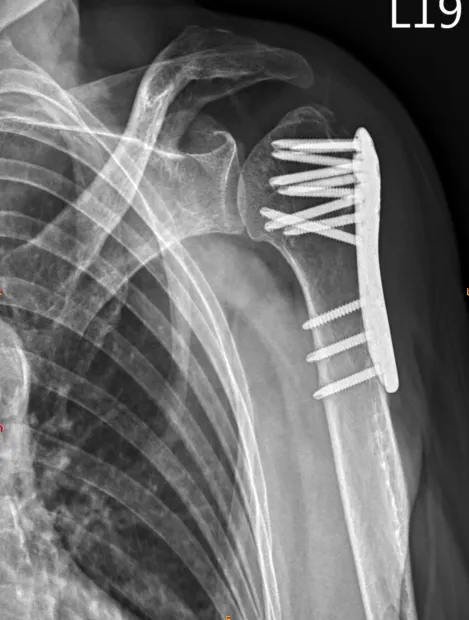

肱骨骨折 是指上臂骨肱骨斷裂的情況,根據骨折的位置和方式,可以分為以下幾種類型:

肱骨頸骨折:骨折發生在肱骨頸部,即肱骨與肩關節相連的部位。

肱骨大結節骨折:骨折發生在肱骨大結節,即肱骨上方的突起部位。

肱骨幹骨折:骨折發生在肱骨的中段或下段。